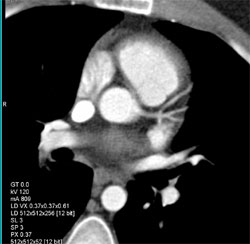

Air in Pulmonary Artery- Be Careful